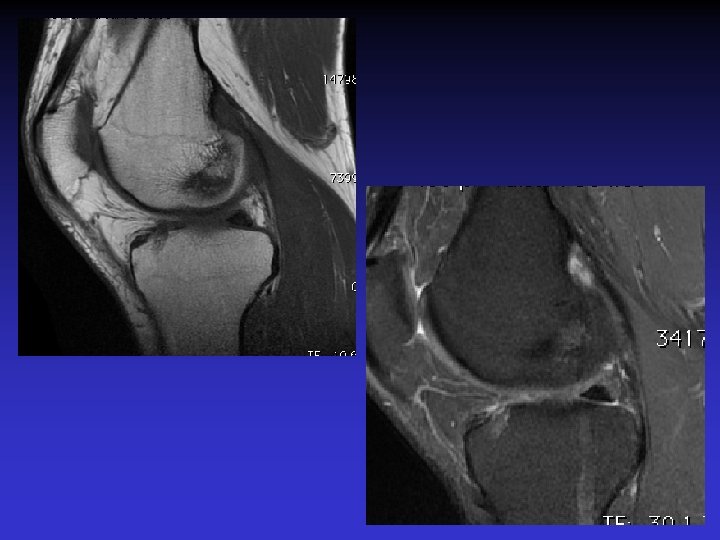

ATTEINTE BILATERALE • Non exceptionnelle • Concomitante ou décalée dans le temps

Mme S… 60 ANS DROIT

Mme S… 60 ANS GAUCHE